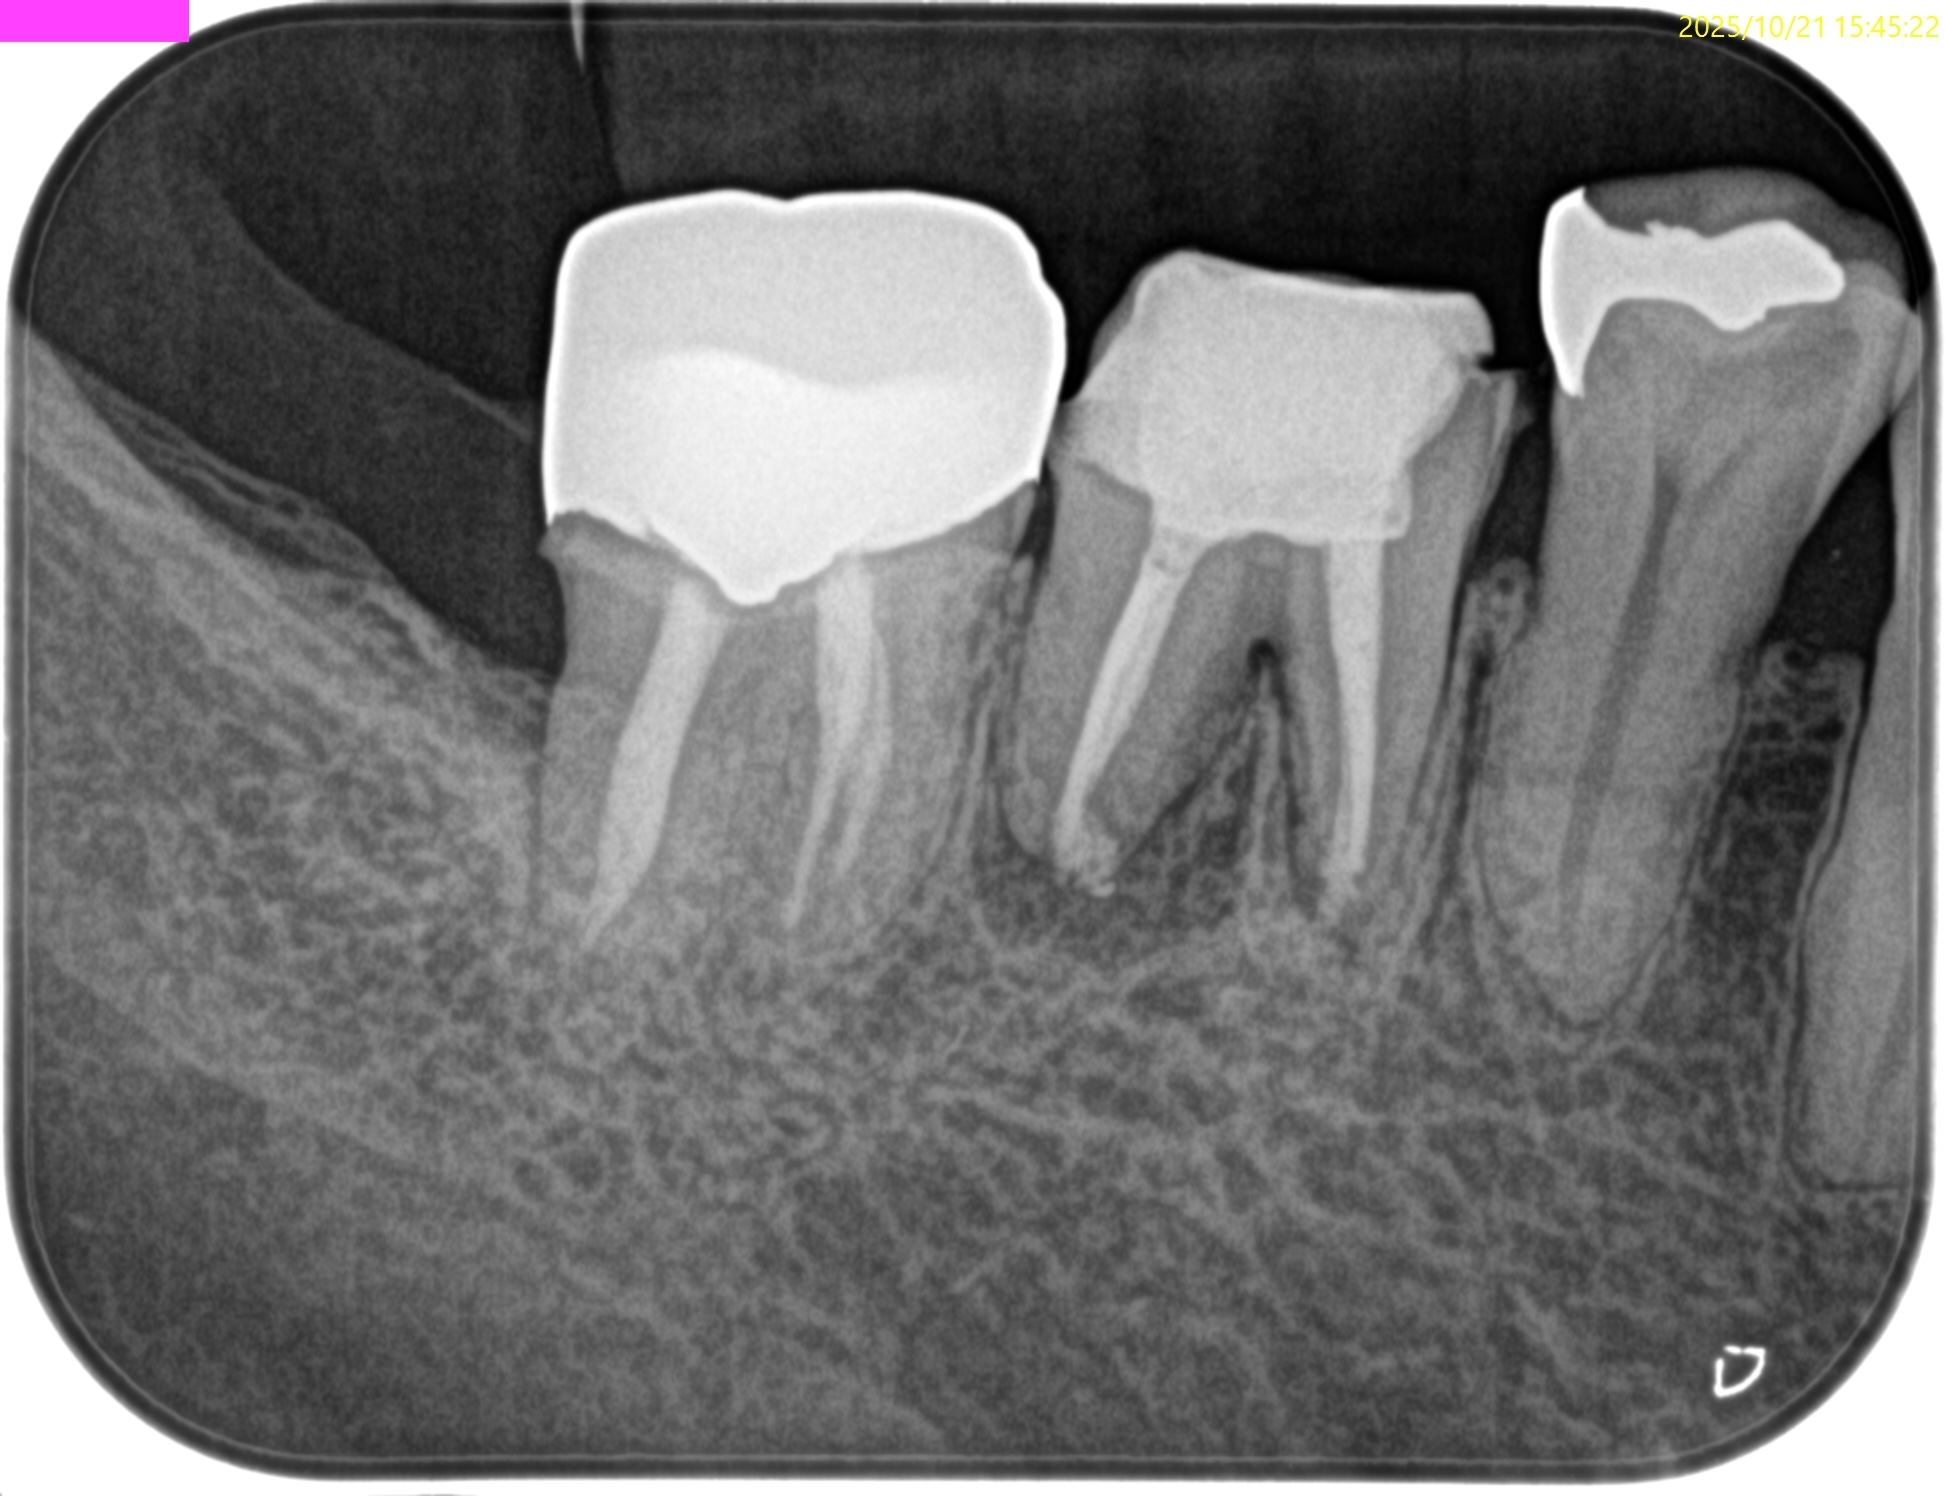

PA(2025.9.16)

根管充填はかなり粗である。

再根管治療でマネージメントが可能そうだ。